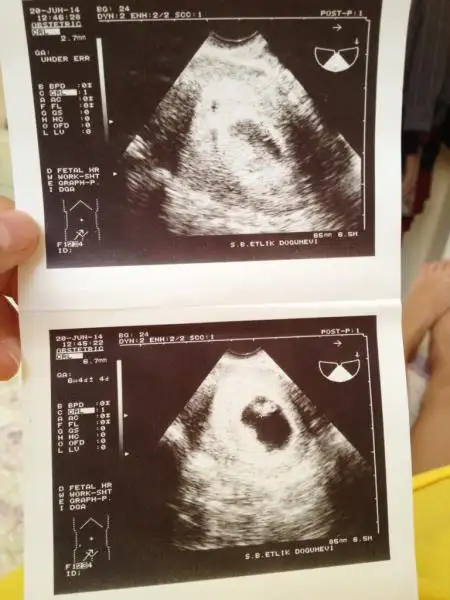

Eki Görüntüle 1176727 Eki Görüntüle 1176728 Eki Görüntüle 1176729 . Dandini bunlar bi öncekiler bgnlü görüntü hastanede kalmş

Kızlat anca yazabilyrm ikizlerim gayet iyilermiş doktor progestan seni mahveder ben sana aynı eş degerde haftada bir iğne vereyim dedi ikizlerin biri 8 haftalık diğeri 7+6 boyları da biri 16.6 mm diğeri 15.5 mm biri sag üst fetüs diğeri sol alt fetüs yazıyo :) bu bebekler bugn yüzümü güldürdüler seviyorum seviyorum kurbaga yavrusuna benzeselerde seviyrm :)